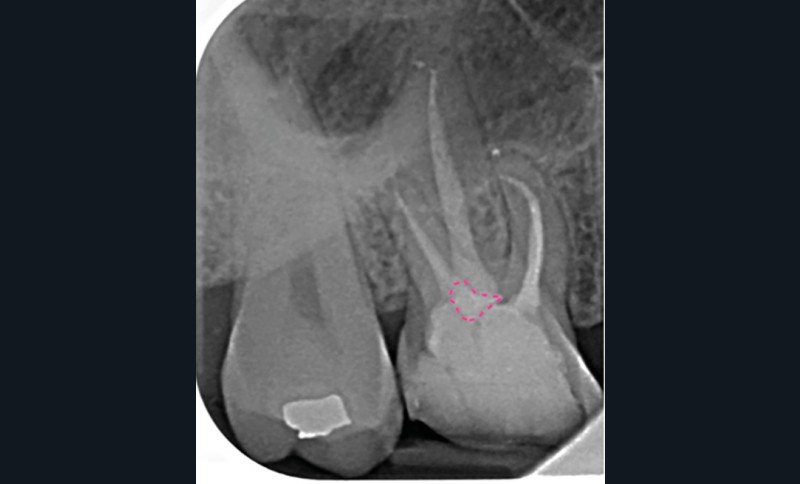

Ce type de perforation est également la plupart du temps iatrogénique et survient lors de la recherche ou de la mise en forme canalaire, lors de la préparation pour un logement de tenon radiculaire. Situées au niveau du plancher pulpaire des dents pluriradiculées, ou au niveau des entrées canalaires des dents monoradiculées ou pluriradiculées, il s’agit le plus souvent de perforations à quatre parois. Si la perforation survient en cours de traitement, elle doit être gérée immédiatement pour un meilleur pronostic (fig. 4). Néanmoins, il est important de prendre en compte l’épaisseur résiduelle du plancher. Si le plancher est trop fin, il ne sera pas possible d’envisager de traiter la perforation.

17. reconstitution coronaire étanche à l’aide d’un CVIMAR ou d’un composite (fig. 5).